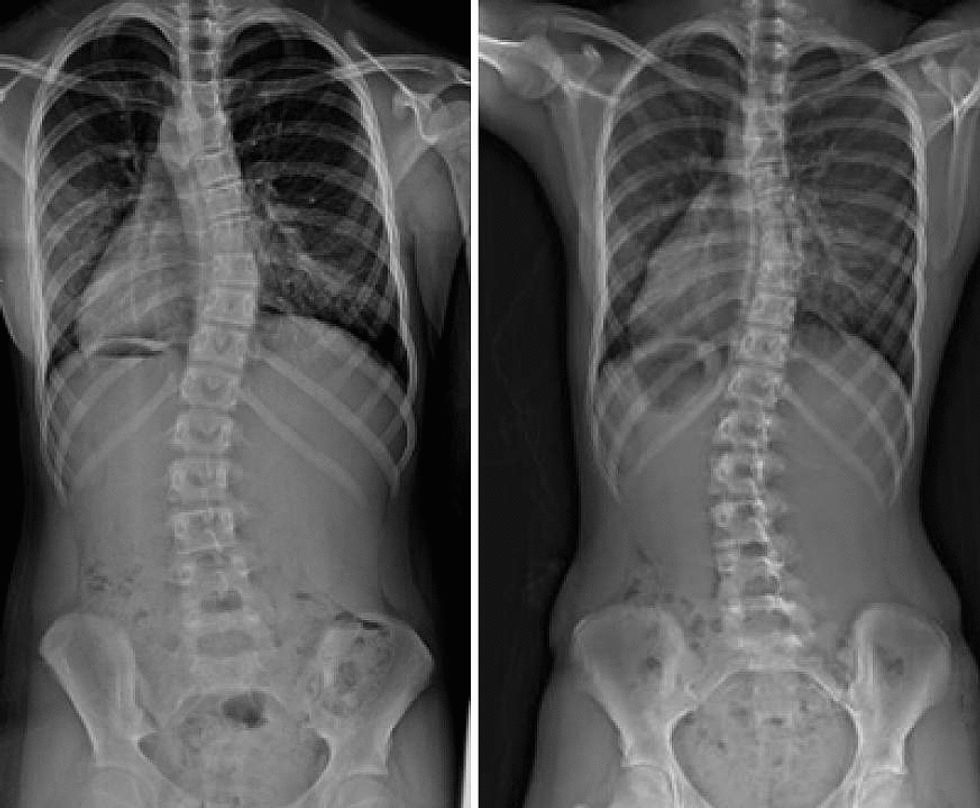

Scoliosis can simply be defined as the abnormal curvature of the spine. On an x-ray, the spine of a person with scoliosis looks like an "S" or a "C". The severity of this condition can vary by person to person, but the majority of those diagnosed follow the same procedures regarding treatment; observation, back brace, then perhaps surgery.

In one of the routine check-ups, my pediatrician made me do the Adam's Forward Bend Test, which required me to bend forward as she checked my spine and back for any abnormalities. That was when she noticed my spine had a curve to it. From there, she referred me to a lab for a spine x-ray, which confirmed her suspicion.

To get an idea of the severity of my scoliosis, my pediatrician referred me to an orthopedic doctor, who had me go through x-rays on my spine and hand to measure the curvatures in my spine, as well determine when would I stop growing. At that time, I didn't even know what to think. It all happened so quickly, and I didn't have to process that there was something wrong with me. Also, I was under the impression that my spine was fine and that it required no further treatment. But, I was wrong.